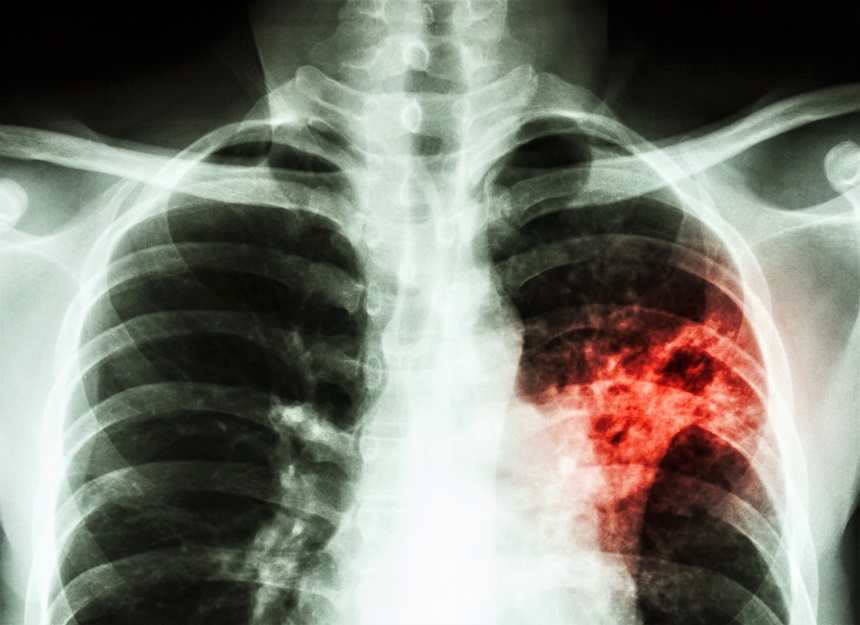

Some painkillers may exacerbate tuberculosis infection

Should you use common drugs like ibuprofen, if you have acquired a TB infection?

Tuberculosis is one of the largest health issues in the world. More than 10 million people fall ill to TB each year, and in 2017 alone, 1.6 million people died from the disease. That makes TB the most deadly single infectious disease in the world. In addition to this, the emergence of multi-drug resistant forms of TB have increased the need for new treatment options.

"One group of mice received TB without treatment, while the other group was treated with the COXi drugs. In the second group, we found up to 10 times more TB bacteria in the lungs. A characterization of the immune system showed that the treated mice had a reduction in a specific type of Th1 T cells that are particularly important in controlling TB," Rasmus Mortensen continues.